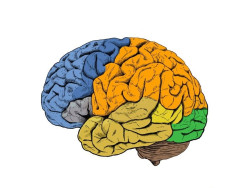

Nuevos datos relacionan las bacterias intestinales con las enfermedades neurodegenerativas

Las enfermedades neurodegenerativas, como el Alzheimer, el Parkinson y la ELA, afectan a millones de adultos, pero los científicos aún no saben cuál es la causa, lo que supone un importante obstáculo para desarrollar tratamientos o medidas preventivas. Un nuevo estudio de la Universidad de Florida, en Estados Unidos, establece, por primera vez, un vínculo entre especies específicas de bacterias y manifestaciones físicas de enfermedades neurodegenerativas.